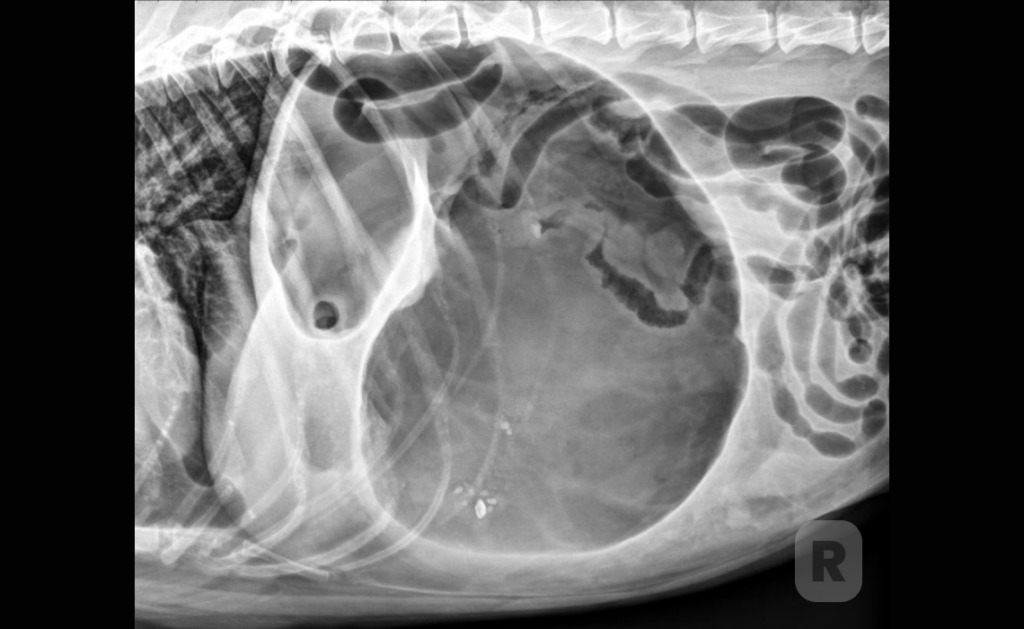

Abdominal Radiography

Findings with the patient in right lateral recumbency include pyloric air entrapment and pyloric

malpositioning that is described as a “double bubble” sign, “reverse C” sign, “boxing glove” sign, “Popeye’s arm” sign, or “Smurf’s hat” sign.

Pneumoperitoneum indicates gastric perforation or gastric trocarization.